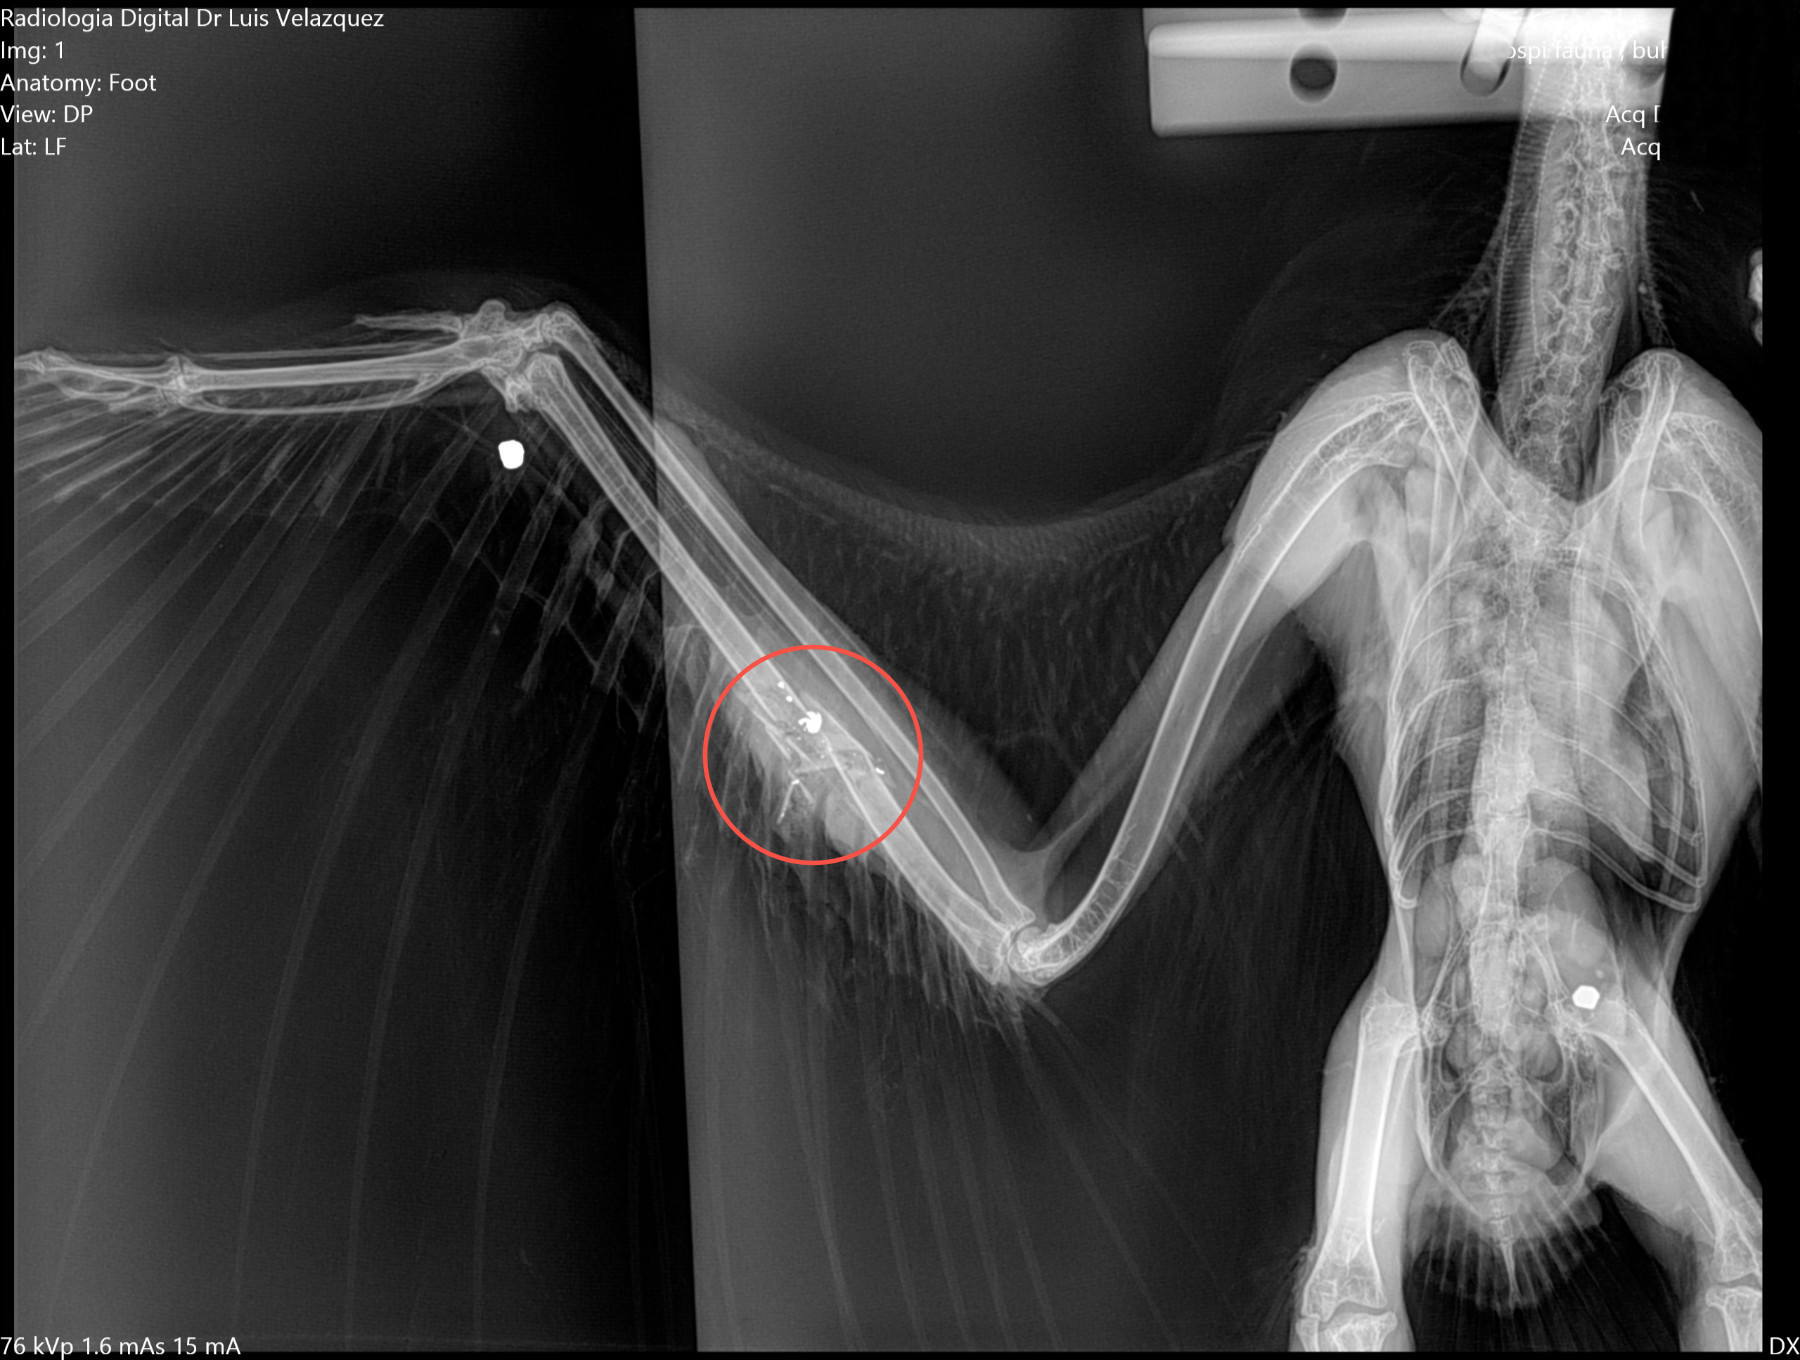

Radiología Digital como Herramienta Complementaria en el Dictamen de Bienes Muebles